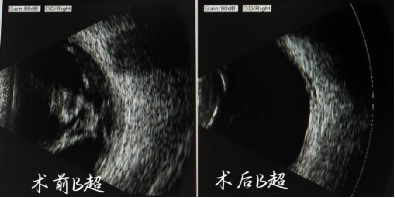

某天陈阿姨右眼视力突然下降,在爱人的搀扶下到眼科门诊就诊,检查结果如同晴天霹雳,陈阿姨右眼由于玻璃体积血导致视力骤降,视力检查仅有0.06,B超提示右眼视网膜大量增殖牵拉,并且左眼视力仅剩部分方位的光感,玻璃体大量陈旧性积血和增殖,眼部病情相当严重。

图源:右眼B超检查结果对比

对于陈阿姨而言,保住右眼视力迫在眉睫,但是由于长期透析,陈阿姨身体消瘦、营养不良,血糖调控困难、全身状态较差,是否能耐受眼科手术、术后可否按要求保持面朝下体位,成为我们不得不面对的问题。